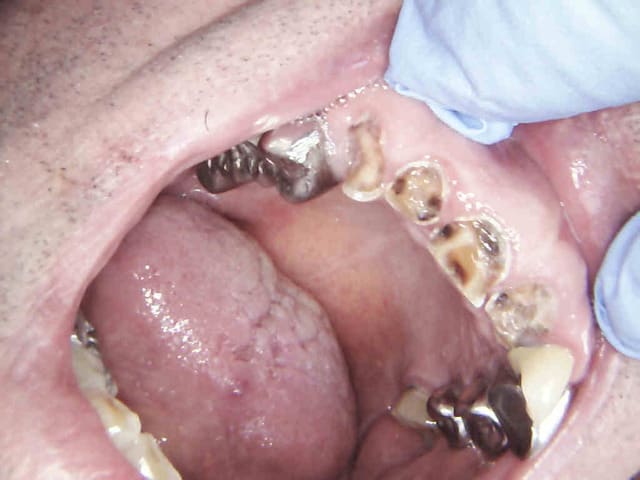

Endo taille empreinte provisoires 2H 30.

Avantage tu peux faire les provisoires et l'empreinte dans la séance et surtout tu peux raser les couronnes ce qui est un réel plus pour les endos surtout avec des pulpes rétractées comme ici ca évite de faire des conneries avec un abord palatin ou on ne voit rien du tout.